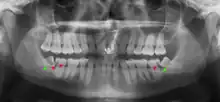

Impacted wisdom teeth are classified by their direction of impaction, their depth compared to the biting surface of adjacent teeth and the amount of the tooth's crown that extends through gum tissue or bone. Impacted wisdom teeth can also be classified by the presence or absence of symptoms and disease. Screening for the presence of wisdom teeth often begins in late adolescence when a partially developed tooth may become impacted. Screening commonly includes a clinical examination as well as x-rays such as panoramic radiographs.

Impacted wisdom teeth are classified by the direction and depth of impaction, the amount of available space for tooth eruption, and the amount of soft tissue or bone (or both) that covers them. The classification structure helps clinicians estimate the risks for impaction, infections and complications associated with wisdom teeth removal.[6] Wisdom teeth are also classified by the presence (or absence) of symptoms and disease.[7]

Impacted wisdom teeth are often described by the direction of their impaction (forward tilting, or mesioangular being the most common), the depth of impaction and the age of the patient as well as other factors such as pre-existing infection or the presence of pathology (cysts, tumors or other disease).[5]: 143–144 Each of these factors is used to predict the difficulty (and rate of complications) when removing an impacted tooth, with age being the most reliable predictor[8] rather than the orientation of the impaction.[9]

If the tooth cannot be assessed with clinical exam alone, the diagnosis is made using either a panoramic radiograph or cone-beam CT. Where unerupted wisdom teeth still have eruption potential several predictors are used to determine the chance of the teeth becoming impacted. The ratio of space between the tooth crown length and the amount of space available, the angle of the teeth compared to the other teeth are the two most commonly used predictors, with the space ratio being the most accurate. Despite the capacity for movement into early adulthood, the likelihood that the tooth will become impacted can be predicted when the ratio of space available to the length of the crown of the tooth is under 1.[5]: 141